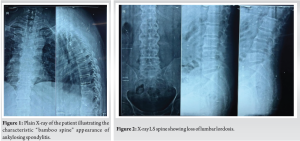

A 52-year-old man presented with a 20-year history of diffuse, non-radiating abdominal pain, localized to the right lower abdomen and aggravated by straining. He was diagnosed with a duodenal ulcer after an endoscopy and began treatment. He also reported 2 months of progressively worsening lower back pain, aggravated by walking and standing, without a history of trauma, tuberculosis, or constitutional symptoms. On examination, he had tenderness over the D11 region of the spine, with limited chest expansion and restricted, painful movements of the cervical and lumbar spine. Straight leg raise test and Faber’s tests were negative, with no motor or sensory deficits. HLA-B27 was positive, while the rheumatoid factor was negative. Radiographs showed loss of lumbar lordosis, with irregularities and erosions at the D11-D12 vertebral bodies (Fig. 1 and 2). Magnetic resonance imaging (MRI) revealed asymmetrical bilateral sacroiliitis, with paravertebral enhancement and syndesmophytes at D11-D12 and L2-L3. The Andersson lesion (AL) was hemispherical, hypointense on T1, and hyperintense on T2 and STIR images, with signs of reactive sclerosis and vertebral end plate erosions (Fig. 3-5). Right sacroiliitis with mild joint space reduction on the left side suggested chronic sacroiliitis. Based on these findings and the positive HLA-B27, a diagnosis of AS with AL was confirmed, with differential diagnoses including Pott’s spine, pyogenic infection, and malignancy.